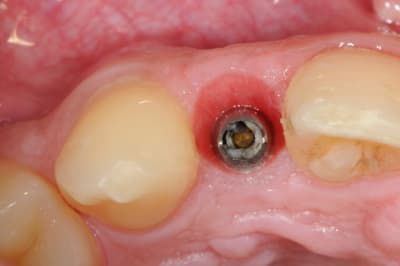

je reviens sur ce cas que j'ai un peu délaissé...

-cicatrisation

-mise en place vis de cica petit diamètre

-ensuite on augmente le diamètre en conservant et en gonflant les tissus gingivaux